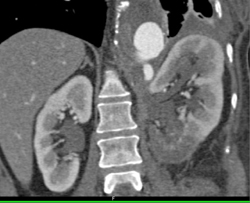

Diagnosis

Blood Clot in Bladder